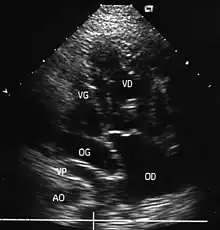

- L'échocardiographie qui est de plus en plus l'examen pratiqué en première intention. Cet examen permet d'affirmer le diagnostic en montrant les anomalies anatomiques, d'apprécier le caractère plus ou moins fonctionnel des shunts cardiaques fœtaux, de rechercher d'autres anomalies associées et dans une certaine mesure d'apprécier le retentissement de la malformation.

- Les coupes échographiques les plus utiles à cette fin sont :

- la coupe parasternale gauche grand axe : elle montre que le vaisseau issu du ventricule gauche (le plus postérieur) se dirige anormalement vers l'arrière et se bifurque précocement. C'est donc le tronc pulmonaire et non l'aorte comme normalement ;

- les coupes sous costales qui montrent bien le trajet parallèle des gros vaisseaux et leur inversion.